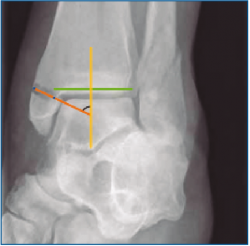

De cada uno, se han obtenido las siguientes mediciones radiológicas: tipo de lesión según Lauge-Hansen, número de maléolos afectados, medida del ángulo talocrural, ratio tibiofibular anteroposterior (AP), presencia o ausencia de superposición de colículos del maléolo interno con el peroneo, ECTF, solapamiento tibiofibular, ángulo de inclinación astragalina, línea de Shenton continua o discontinua, espacio claro medial y ángulo principal a estudio, el ángulo crurofocal medial (ACFM). Para analizar el ángulo principal, se debe obtener una línea perpendicular a la superficie articular tibial (del mismo modo que para el primer paso de la medición del ángulo talocrural); una vez hecho esto, se traza una línea entre el punto más medial y más lateral del trazo de fractura del maléolo interno en el origen tibial. El ACFM es el formado por esta línea y la perpendicular a la superficie articular tibial, y estará comprendido en un arco de valores posibles entre 0 y 180° (Figuras 1 y 2).

Figura 2. A: obtención de una perpendicular a la superficie articular; B: superposición de un brazo del ángulo a la perpendicular; C: situación del otro brazo en la línea formada entre los orígenes tibiales; D: medición completada.